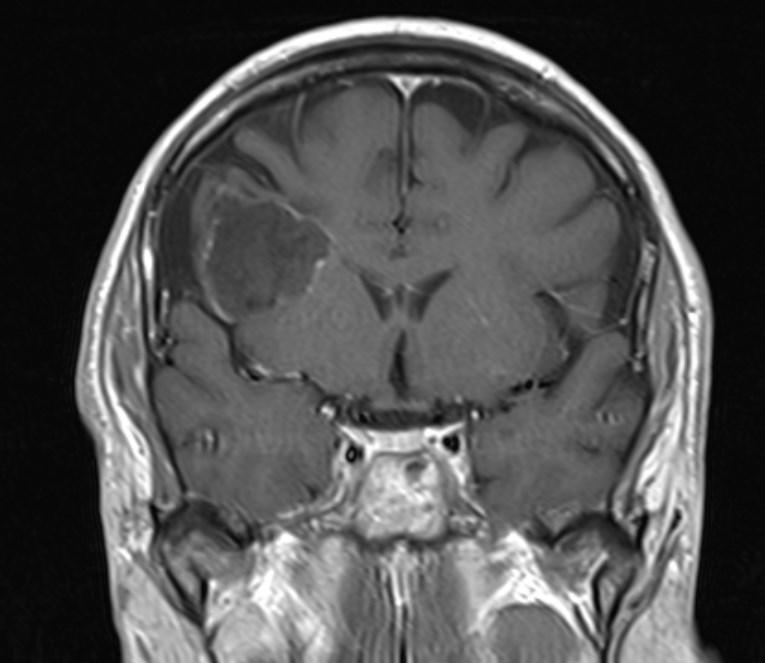

*50-year-old male present with headache.

What is the most likely diagnosis?

Answer: Primary hydatid cyst of right frontal lobe.

MR images revealed Gharbi type V hydatid cysts in right frontal lobe.

Gharbi classified hydatid cyst ultrasonographic images into 5 types: Type 1, walled, unilocular, anechoic; type 2, separated membranes; type 3, multisepta, daughter vesicles; type 4, heterogenic, hypo-hyperechogenic; type 5, calcification of a section of the wall or completely calcified (4). The cysts characteristically have three components: Pericyst, Exocyst, and Endocyst.